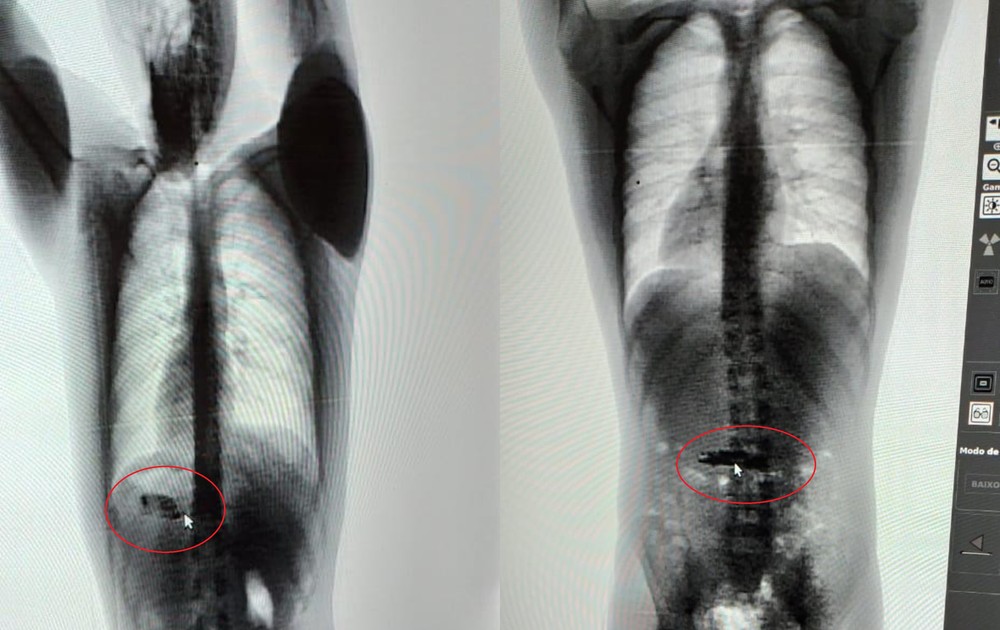

Dois presos provisórios da Unidade Penitenciária Evaristo de Moraes, em Sena Madureira, interior do Acre, foram flagrados com celulares no estômago na tarde desta quarta-feira (22). Os aparelhos foram vistos quando os presos eram transferidos de pavilhão.

Os detentos foram submetidos ao aparelho scanner corporal, que detectaram os celulares. O Instituto de Administração Penitenciária do Acre (Iapen-AC) informou que os presos estavam no bloco de observação, local para onde são levados os suspeitos recém presos.

Ainda segundo o Iapen-AC, os dois presos apresentaram nervosismo durante a transferência. Diante da suspeita, os policiais penais levaram os detentos para o scanner corporal e acharam os celulares.